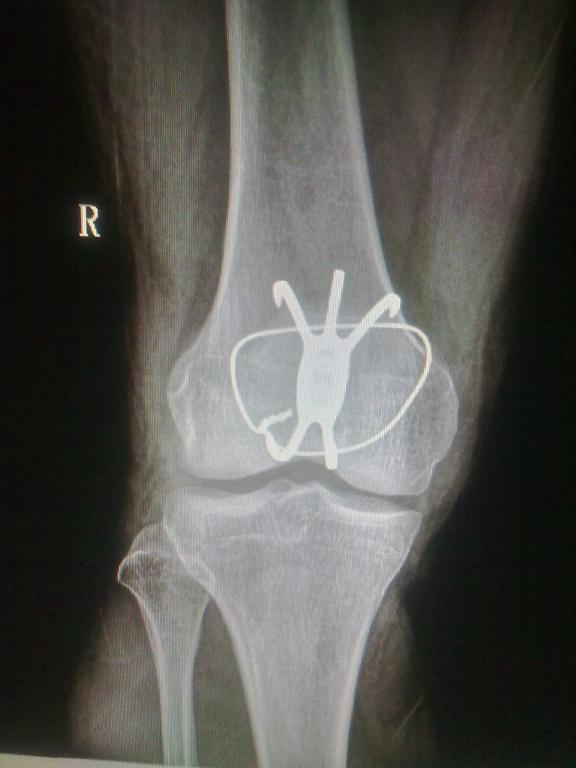

做的第一例髌骨骨折髌骨爪内固定。请大家看看!

患者男性.43岁,因骑自行车致右下肢受伤.***就诊,查体示:右膝关节肿胀明显.不能主动伸膝,皮下淤青,浮髌征(+).末梢感觉血运好!是个髌骨下极骨折!(术前片拍反了)前天手术完,今天发上来给老师们看看,有什么可指导的地方,谢谢!

做的漂亮,关节面很平。

手术做得不错,钢丝是不是有点多余,再一个材质不同要考虑电解问题

有点画蛇添足的了,用髌骨爪就不要用钢丝捆了,这样做在活动膝关节的时候钢丝容易折断。手术做得不错。